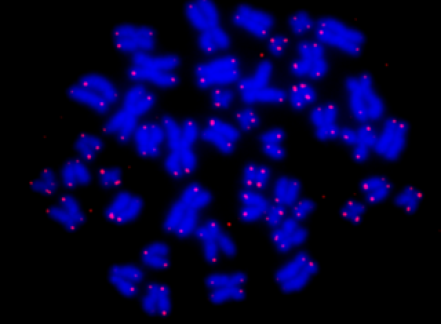

• 微重力环境能杀死癌细胞?

2019年,悉尼科技大学由Joshua Chou博士带领的生物工程团队宣布,他们提取了乳腺癌、卵巢癌、肺癌和鼻癌细胞四种不同类型的癌细胞,并放入地面模拟的微重力环境中,24小时后,这些癌细胞中有80%至90%死亡,也就是说,微重力环境能杀死癌细胞!